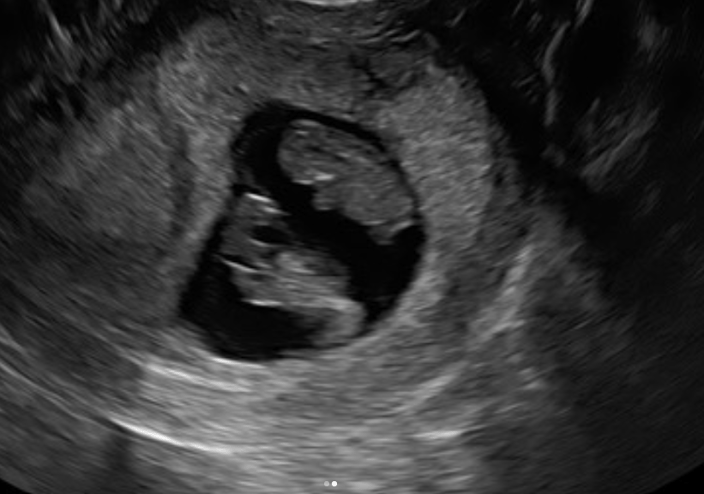

Two heartbeats

At seven weeks and four days, we went back to the clinic for another scan, and we were both holding hands, in a sort of desperation, whilst I laid on the bed. The lady doing the scan said ‘I have something to tell you’ and I instantly thought, oh it’s gone, isn’t it? But she turned the monitor around and there were TWO little heartbeats. And I suppose, this was a really weird reaction, but we just laughed. I guess almost in disbelief. We had wanted a family, we had finally gotten pregnant, and it wasn’t with just one baby, it was two. We were so lucky, the embryo had split.

That first heartbeat appointment at Care Fertility Sheffield turned into double the joy — the embryo had split, and they were suddenly preparing for twins.